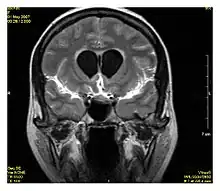

Neuroimaging

MRI is the investigative tool of choice for neurological cancers over CT, as it offers better visualization of the posterior cranial fossa, containing the brainstem and the cerebellum. The contrast provided between grey and white matter makes MRI the best choice for many conditions of the central nervous system, including demyelinating diseases, dementia, cerebrovascular disease, infectious diseases, Alzheimer's disease and epilepsy.[31][32][33] Since many images are taken milliseconds apart, it shows how the brain responds to different stimuli, enabling researchers to study both the functional and structural brain abnormalities in psychological disorders.[34] MRI also is used in guided stereotactic surgery and radiosurgery for treatment of intracranial tumors, arteriovenous malformations, and other surgically treatable conditions using a device known as the N-localizer.[35][36][37] New tools that implement artificial intelligence in healthcare have demonstrated higher image quality and morphometric analysis in neuroimaging with the application of a denoising system.[38]